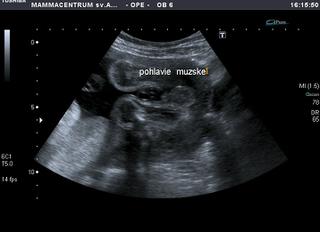

@paula1234 ahoj, chcem sa spytat k tej polohe vasho krpca... dr. nepocita s tym, ze by sa este otocil? planuje sa sekcia hned takto v 30. tt? ja mam taky blby pocit, ze sme i my krizom cez brucho, podla pohybov, resp. kopancov to citim, na dvoch miestach horizontalne cez brucho vzdialenych asi 15 - 20cm od seba... to znamena ruky a nohy... na UTZ idem az za 3 t, to budem v 31.tt...